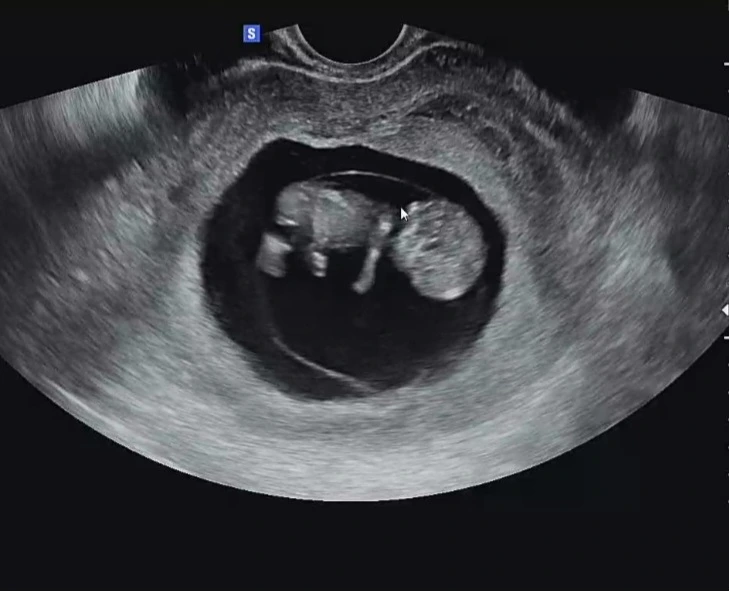

그래도 지난주 금요일에 뱃속에 둘찌가 팔, 다리도 길쭉길쭉 생겨나고 주수에 맞춰 잘 성장하고 있는 모습을 봐서 신기하고 다행스러웠다.